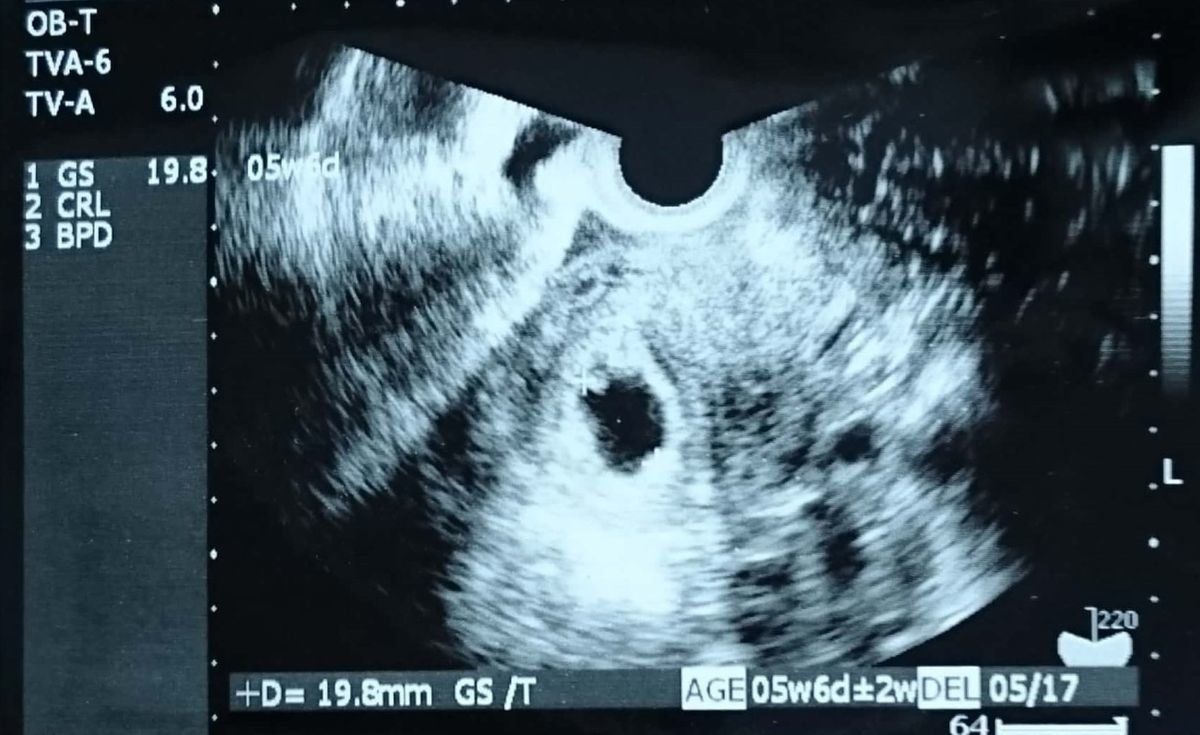

妊娠6週のエコー写真 ようやく心拍を確認するも、まだ気が抜けない時期

D(胎嚢):19.8mm

めまいに加えて、つわりが出始めました。不正出血から1週間後の検査で、胎嚢の中に胎芽と心拍を確認。左上にちょこんと、くっついています。前回、心拍確認後の流産だったため、「もう少し様子を見ようか」と、この時点ではまだ母子手帳をもらってくるようには言われませんでした。なお、エコー写真に記載される週数は、胎嚢、胎芽の大きさで計るために、1週間たってもまだ5週と表示されています。